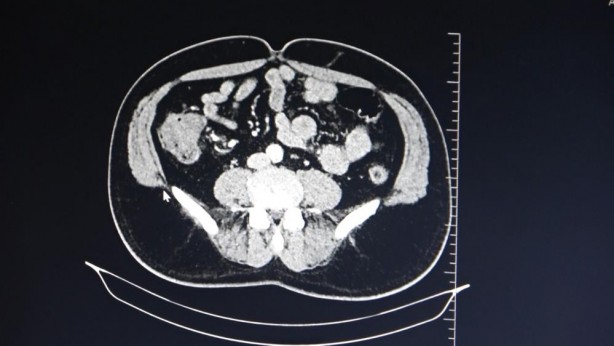

Foto - Uzmanlardan kolon kanserine karşı uyarı